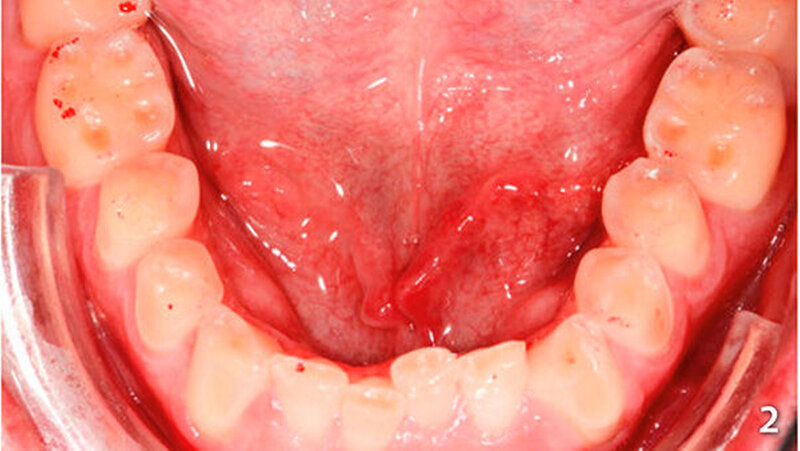

Der Patient wies an allen Frontzähnen sowie an den Seitenzähnen des Unterkiefers starke erosive Defekte auf (Abb. 1-3). Der Patient störte sich vor allem am Erscheinungsbild seiner Oberkieferfrontzähne und dem Engstand im Unterkiefer-Frontzahnbereich. Er wurde über verschiedene Therapiemöglichkeiten ausführlich aufgeklärt und entschied sich für direkte Rekonstruktionen mit Komposit. Im Februar 2016 erfolgte die Versorgung mit Kompositrestaurationen, wie folgt beschrieben.